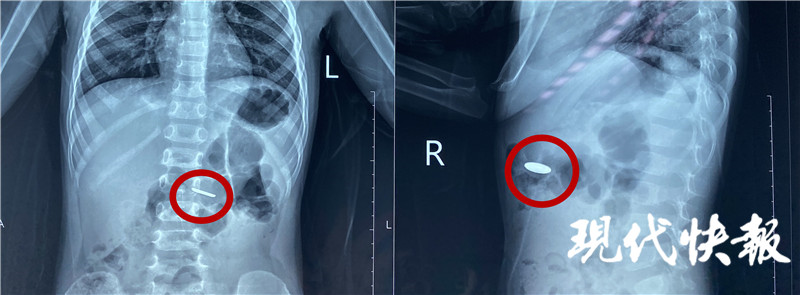

4月20日,江蘇淮安,小豪的家人在收納玩具的時候,發(fā)現(xiàn)常用的遙控器里的一顆紐扣電池不見了,家人的第一反應(yīng)是電池被小豪吃了,趕緊帶著他前往醫(yī)院。經(jīng)過緊張的手術(shù),醫(yī)生從2歲男童小豪(化名)的小腸內(nèi)取出一枚紐扣電池,電池周圍的腸壁被腐蝕發(fā)黑。

“當(dāng)時拍了片子發(fā)現(xiàn)電池在胃部,消化內(nèi)科的醫(yī)生及時給他做了胃鏡檢查,這個電池比較小,已經(jīng)快速排空進入了小腸,胃鏡沒有發(fā)現(xiàn)電池。后來又拍片檢查,確認電池已經(jīng)進入小腸,就轉(zhuǎn)入外科進行手術(shù)治療。”淮安市婦幼保健院小兒外科主治醫(yī)師顧春暉說。

完善手術(shù)準備,醫(yī)生通過腹腔鏡將電池取出。“這個手術(shù)本身比較困難,因為這個電池非常薄,直徑只有1厘米左右,小腸非常長,我們用了很長時間才找到這個電池,電池附近的腸道黏膜已經(jīng)發(fā)黑,形成了化學(xué)性的腐蝕,如果時間再長一點可能造成穿孔等一些非常嚴重的后果。”顧春暉說。